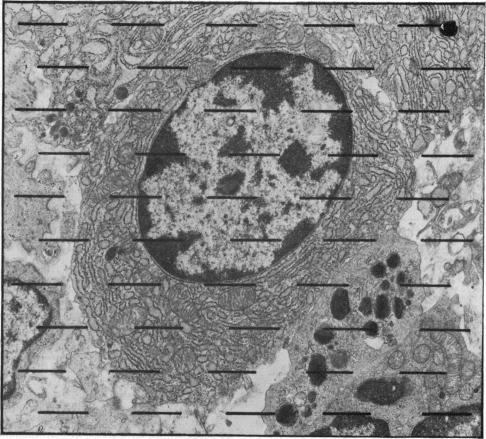

乳糜泻患者浆细胞的超微结构分析。

Ultrastructural analysis of plasma cells in coeliac patients.

By accurate morphometry the length of the rough endoplasmic reticulum (RER) was estimated in electron micrographs of a population of jejunal plasma cells in biopsies obtained from normal volunteers, untreated coeliac disease patients, and coeliac disease patients treated for one year on a gluten free diet. Increase in length or hypertrophy of the endoplasmic reticulum is an indication of increased protein synthesis of the cell (Ghadially, 1977). An increase compared with normal length was demonstrated in the mean length of the plasma cell rough endoplasmic reticulum in plasma cells obtained from both groups of coeliac patients. This estimate of increased protein production--in this case immunoglobulin--indicates an increase in the immunological activity of plasma cells even after treatment and suggests not only a reaction to dietary gluten but probably to other antigens also.

通过精确的形态测量法,在取自正常志愿者、未经治疗的乳糜泻患者以及接受无麸质饮食治疗一年的乳糜泻患者的活检组织中,对空肠浆细胞群体的电子显微照片中的粗面内质网(RER)长度进行了估计。内质网长度增加或肥大表明细胞的蛋白质合成增加(加迪亚利,1977年)。两组乳糜泻患者的浆细胞中,浆细胞粗面内质网的平均长度均显示出较正常长度有所增加。这种蛋白质产生增加的估计——在这种情况下是免疫球蛋白——表明即使在治疗后浆细胞的免疫活性也有所增加,这不仅提示了对饮食中麸质的反应,可能还提示了对其他抗原的反应。